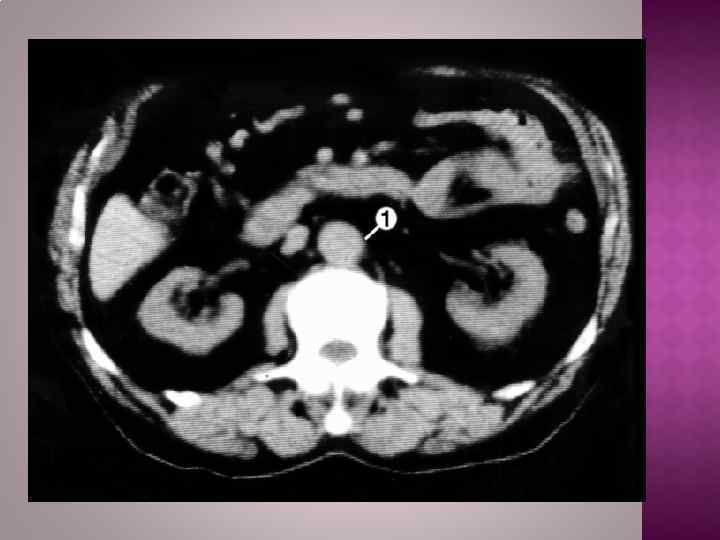

Рентгенологическим признаком аневризмы грудной аорты является наличие гомогенного образования с ровными четкими контурами, не отделимого от тени аорты и пульсирующего синхронно с ней. Трансторакальная эхокардиоаортография дает возможность выявить аневризмы восходящего отдела и дуги аорты, определить их размеры, наличие фенестрации интимы и расслоения аорты, аортальной регургитации. Чреспищеводная эхокардиоаортография позволяет еще лучше распознать патологию аортального клапана, синусов Вальсальвы, устий коронарных артерий, тубулярной части восходящей аорты, а главное — диагностировать расслоение аорты с выявлением внутренней мембраны и проксимальной фенестрации. Компьютерная томография и магнитно-резонансная ангиография позволяют определить локализацию и размеры аневризмы, наличие расслоения аорты и внутрианевризматического тромба, дать характеристику стенки аорты. Рентгеноконтрастная аортография по-прежнему является «золотым стандартом» в диагностике аневризм аорты. При грудных и особенно расслаивающих аневризмах необходимо выполнять контрастирование всей аорты (панаортография) с определением локализации аневризмы, взаимоотношения ее с магистральными ветвями, наличия фенестрации и расслоения.